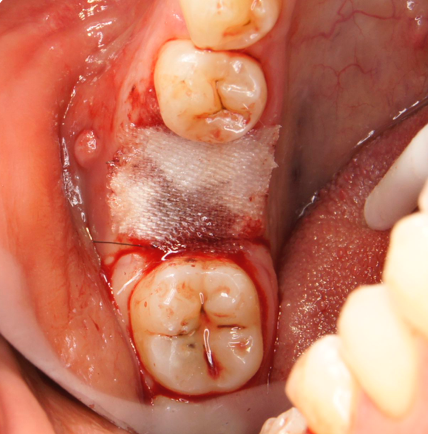

Während oder nach oralen Operationen, von der Extraktion von Zähnen bis hin zu rekonstruktiven Eingriffen, oder Implantationen, bietet BloodSTOP® iX eine schnelle und vorübergehende Kontrolle von Oberflächenblutungen.

BloodSTOP® iX absorbiert schnell Blut und verwandelt sich in ein klares Gel, um die Wunde mit einer transparenten Schutzschicht zu versiegeln, Blutplättchen zu binden und zu aktivieren, sowie die Gerinnung und Wundheilung zu unterstützen.

Anwendungsbeispiele